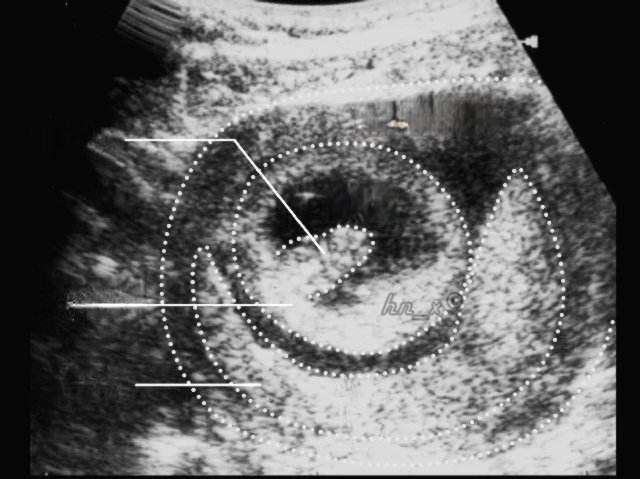

怀孕50多天,孕囊在长、胎芽没长、没有胎心,胎儿是不在了吗?

怀孕50多天,孕囊在长、胎芽没长、没有胎心 这种情况可能意味着胚胎停止发育,也就是所谓的“空囊” 。然而,这并不一定意味着胎儿已经不存在了。

在正常情况下,怀孕50多天时,孕囊直径应该在1.5-2.5厘米之间,胎芽长度约为0.5-1.5厘米,并且能够检测到胎心搏动。 如果孕囊在增长,但没有胎芽和胎心,这可能表明胚胎发育异常或停止发育。